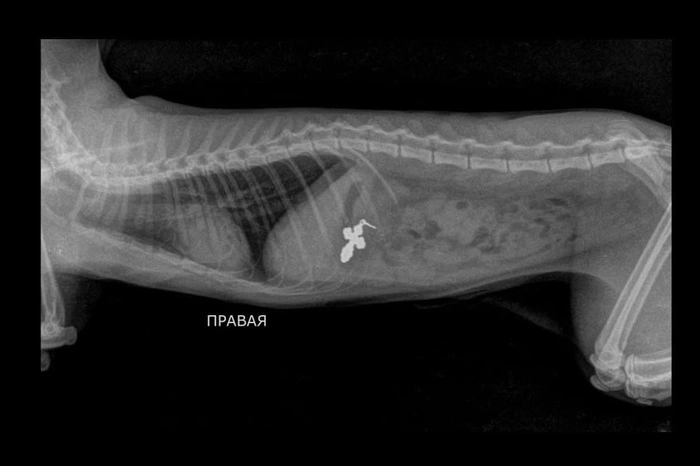

Как выяснилось, Марсик проглотил нательный крестик хозяина. Мужчина рассказал, что потерял его 10 дней назад, когда снял и оставил на столе. Возможно, котенок заигрался с веревочкой и проглотил её вместе с крестиком.

— Крестик был большой, поэтому он не продвигался через сфинктер из желудка в кишечник. Нитка была в самом кишечнике. Эндоскопически достать нитку нельзя было, ее удерживал крестик. Поэтому понадобилась полостная операция, — сообщила ветеринарный врач Степанова.

Операция прошла успешно. Ветврач достала из котенка 30-сантиметровую веревочку и крестик размером 14х25 мм. Сейчас Марсик чувствует себя хорошо, уже начал есть.